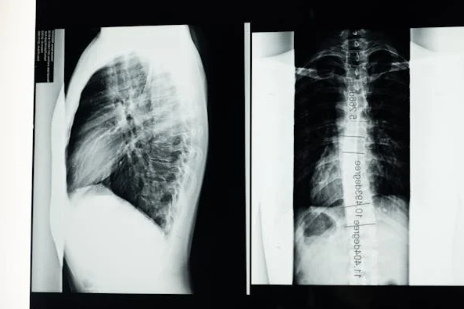

척추측만증은 신체 검사, 엑스레이, MRI 검사를 통해 진단됩니다.

- 엑스레이: 엑스레이는 척추의 측만증 정도를 정확하게 보여줍니다.